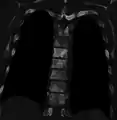

Sclerosis of the bones of the thoracic spine due to prostate cancer metastases (CT image)